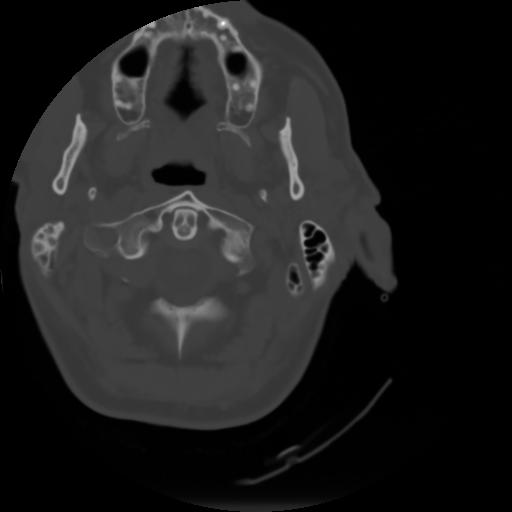

3 CEREBRO,,Axial,3.0,CEREBRO,,